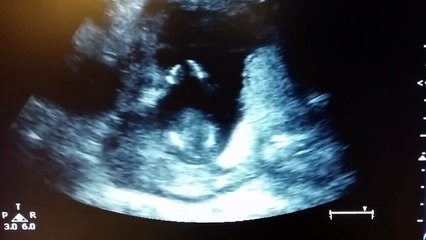

Dentro del útero, operan a un bebé que tenía una malformación